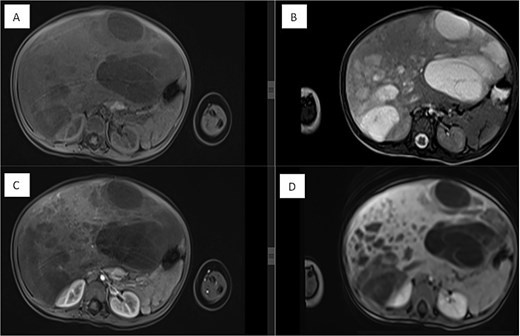

A right-sided hepatectomy was initially planned; however, intraoperatively, the tumor was resected with a safe margin while preserving unaffected liver tissue. Postoperative liver volumetry confirmed adequate remaining liver volume (40%) (Fig. 3). Surgery was completed without complications.

Triphasic CT examination of the abdomen post-right hepatectomy. (A) The axial view shows a clear operative bed with no residual enhancing lesions or collections. The (B) coronal view demonstrates compensatory hypertrophy and enlargement of the left hepatic lobe. Herniated bowel loops are visible, filling the right hypochondrial subphrenic region.